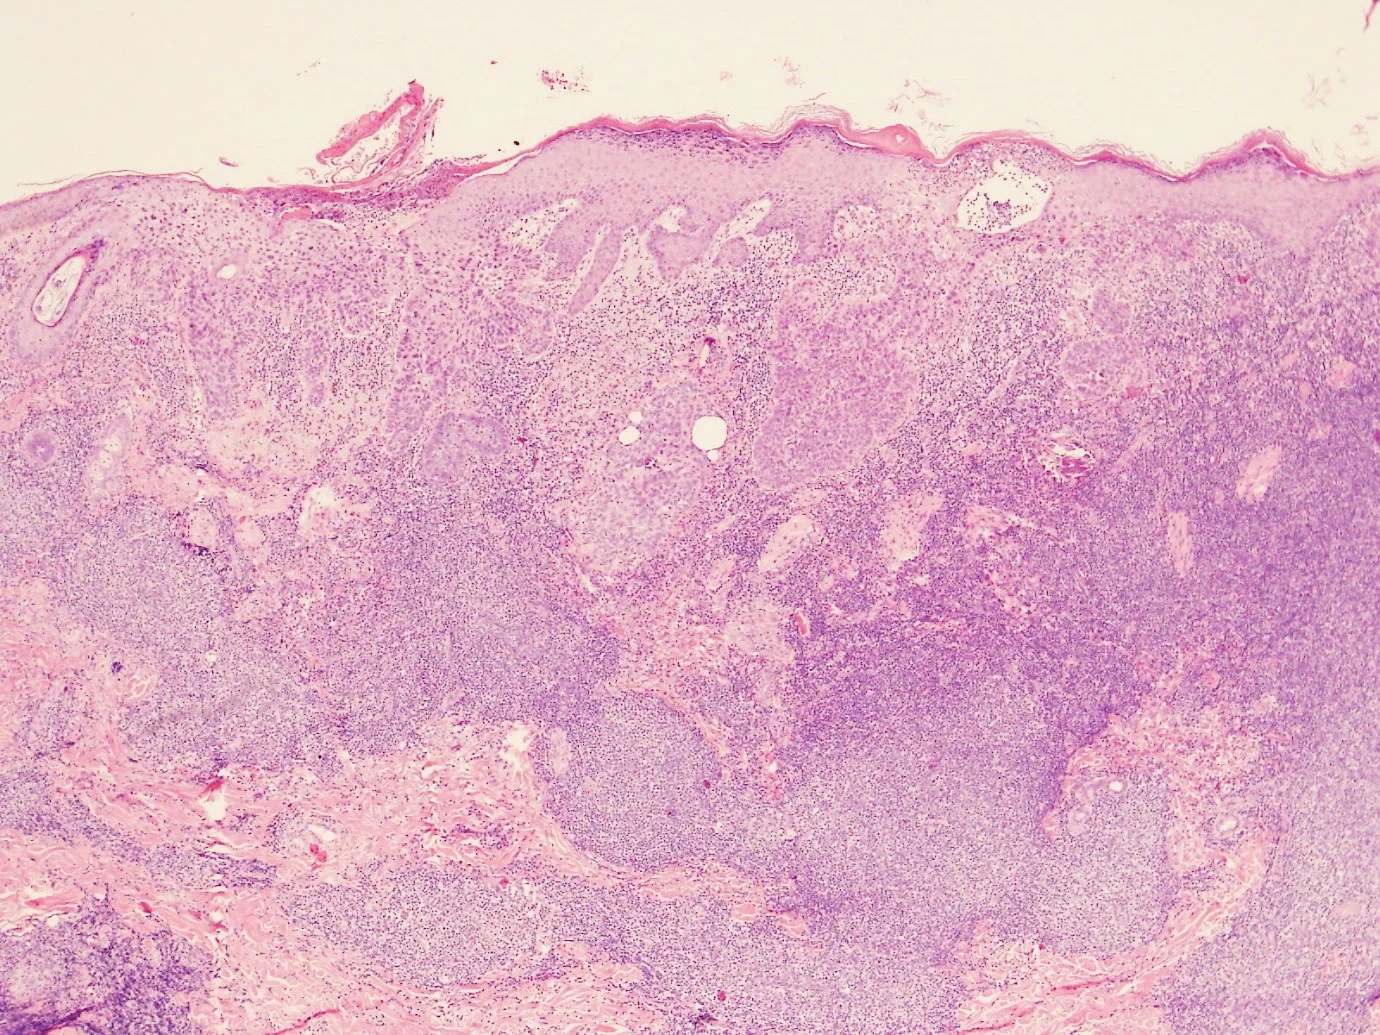

66year old male, presented with three hyperkeratotic scalp lesions, one of which is demonstrated below.

CD20

CD21

D10

BCL2

BCL6

CD79a